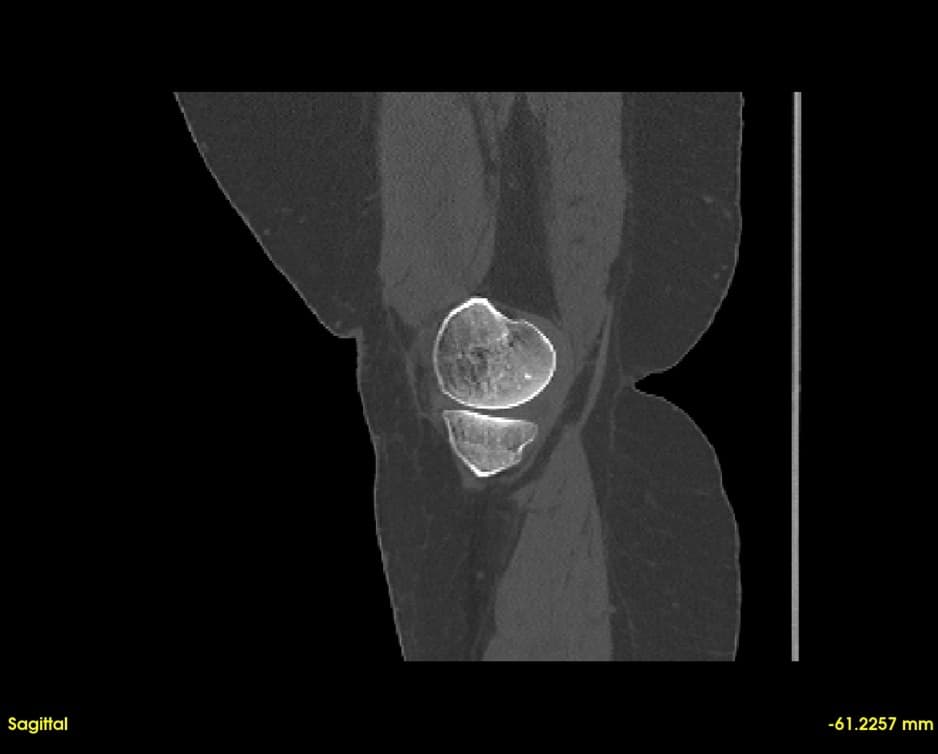

Simultaneous axial, sagittal, and coronal views. Navigate through slices with synchronized cross-referencing.

Explore slices with multi-planar reconstruction views

Quickly visualize and analyze anatomical structures from CT and MRI scans. Identify abnormalities with precise 3D visualization.